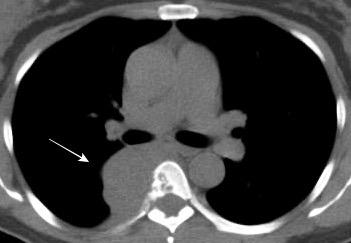

102. HEMATOMA MEDIASTÍNICO.

Anticoagulación mal controlada.

(incluye hemopatía)

Resucitación “vigorosa”

Postcirugía

Hematoma infectado

Seudoaneurisma

Rotura de conducto linfático

Catéter(V. Subclavia, etc.)

Biopsia

Mod. de Brandt 2007